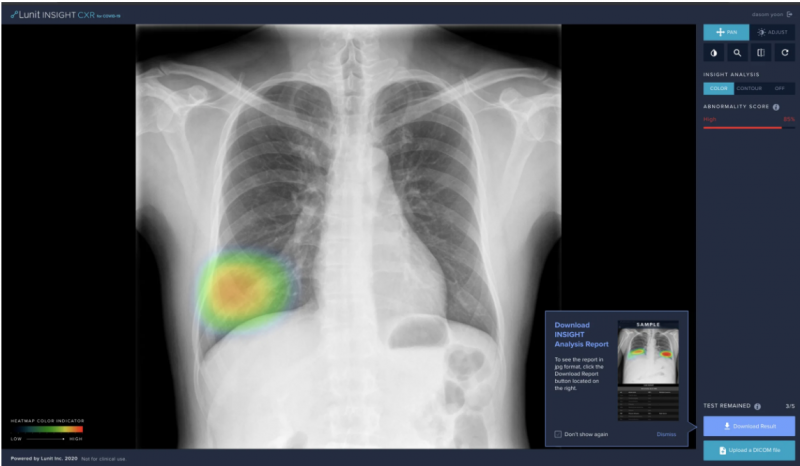

Coronavirus is known to cause pneumonia, which can be found as “consolidation” on chest X-ray images. The software, developed by Lunit, is an AI solution for chest X-ray analysis, detecting 10 different radiologic findings including lung nodule, consolidation, and more with 97-99 percent accuracy. For the online release, the company is providing consolidation findings only, which is suggestive of coronavirus-related pneumonia.

In light of the current outbreak, Lunit has released a special version of Lunit INSIGHT CXR specific for coronavirus, at www.lunit.io/covid19. Anyone can upload chest x-ray DICOM image files and get real-time analysis results conducted by Lunit INSIGHT, for free, with coronavirus-related findings displayed by the algorithm as “consolidation.”